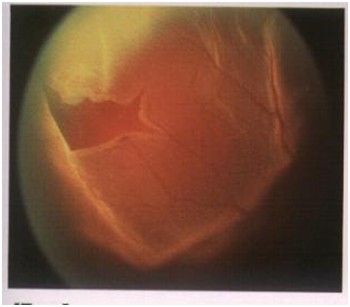

眼底疾病诊治依托北京色漫网 著名眼底病专家,不定期进行门诊、手术,拥有一批经验丰富、技术过硬的核心团队。引进先进的蔡司眼底造影系统、德国蔡司最新型号Lumeral T手术显微镜、美国Alcon Accurus 2500转高速玻切机、德国蔡司第四代CIRRUS OCT光学相干断层扫描仪等大型检查及治疗设备,应用现代高科技手段和专家团队技术力量,提供眼底全套检查项目,重点开展玻璃体、视网膜疾病手术及激光治疗,诊疗项目涉及玻璃体切除治疗玻璃体积血、简单或复杂性视网膜脱离、严重眼外伤、糖尿病视网膜病变、晶体异常、黄斑病变、视网膜下新生血管膜、化脓性眼内炎、视网膜肿瘤等多种复杂疑难眼底疾病,其中在糖尿病视网膜病变复杂性视网膜脱离、黄斑病变、眼外伤的诊断及手术等疑难眼底疾病方面有独到的建树。